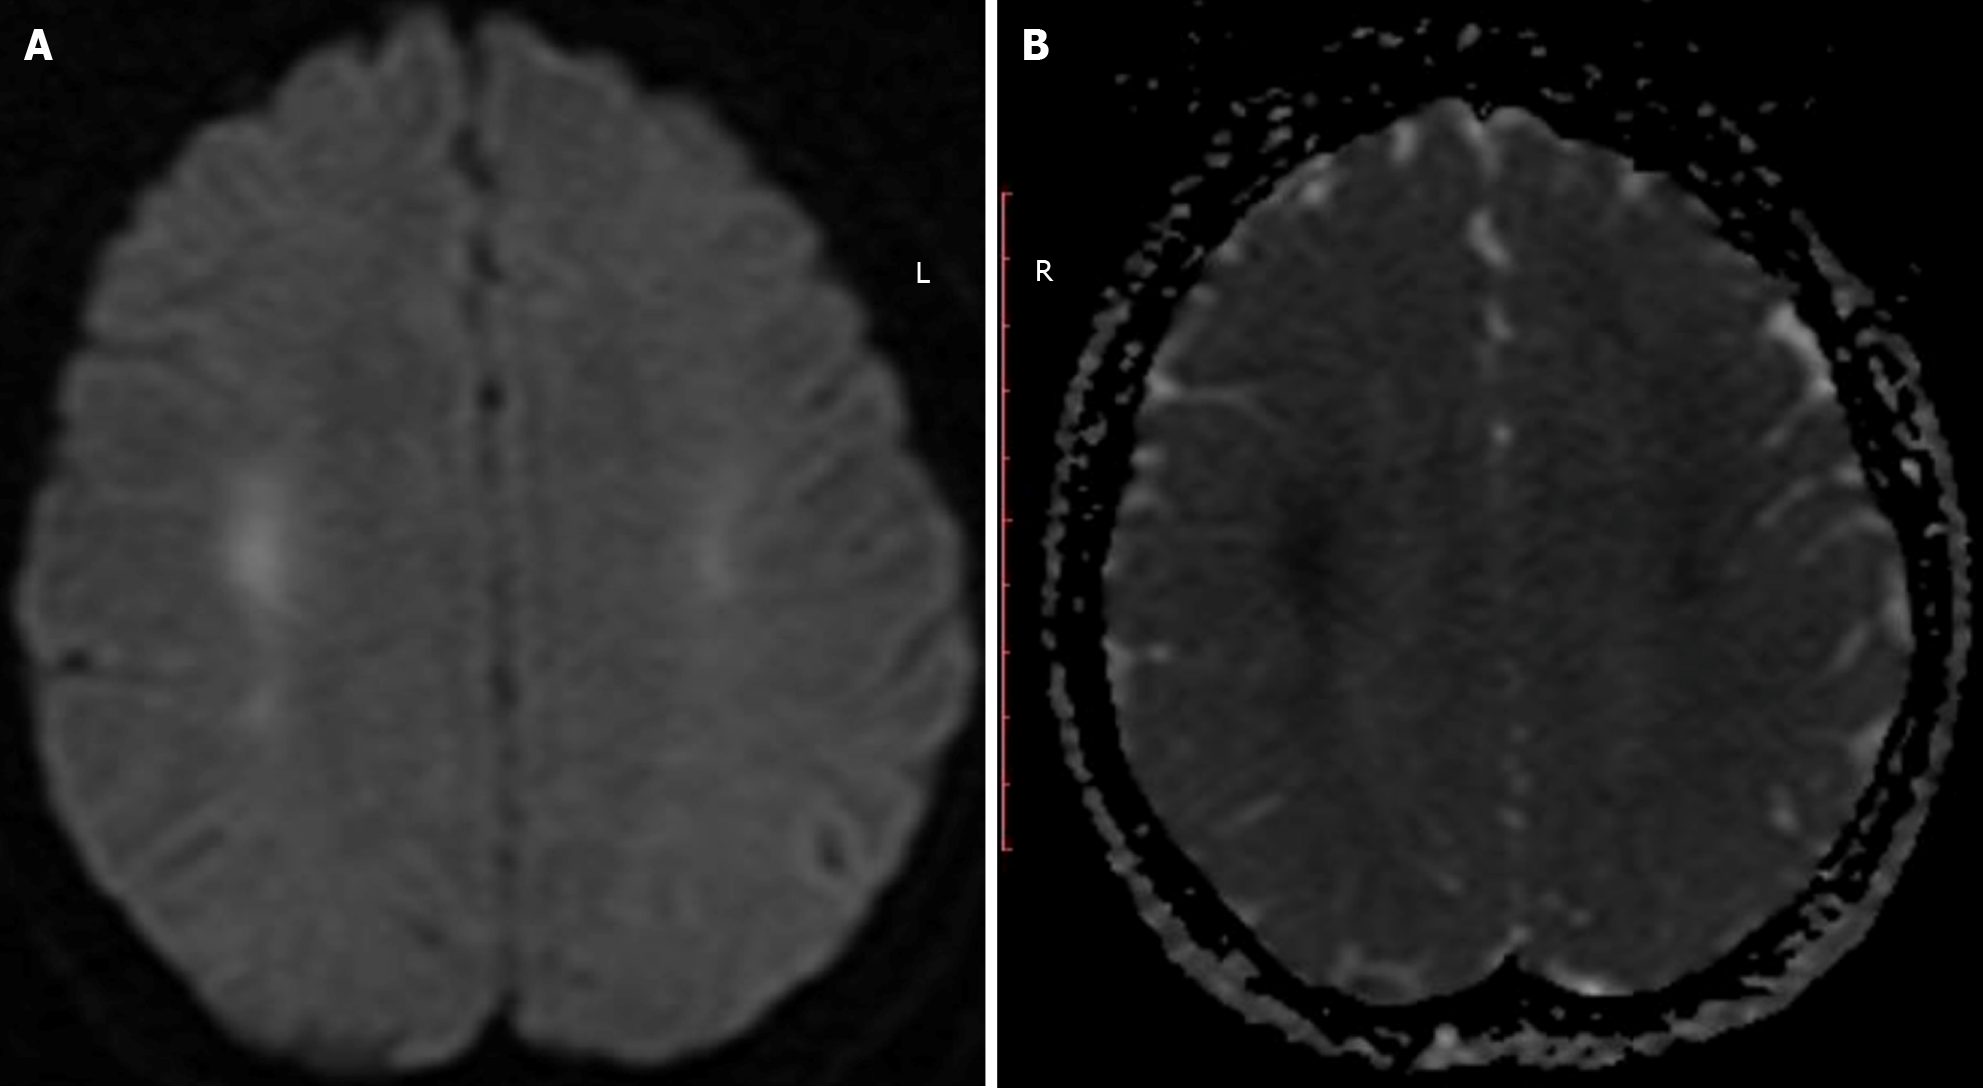

Fluid attenuated inversion recovery (FLAIR) sequence of magnetic resonance imaging (MRI) shows hyperintensities involving the basal ganglia, cortex and white matter (Figure 3A). Diffusion-weighted (DW) imaging, shows areas of restricted diffusion (Figure 4). Diffusion-weighted imaging (DWI) requires absolute diffusion coefficient map confirmation to avoid T2 shine-through artifacts. Watershed infarcts also may be seen[23]. The presence of multilobar alterations on DWI MRI images correlate with poor outcome[24]. The optimal window period for DWI is 24–72 hours, because it may report false-negatives in the hyperacute stage. In the subacute phase, the DWI hyperintensities decrease, and extensive FLAIR hyperintensities can be seen in deep grey matter[21]. In the chronic phase (>3 weeks), diffuse atrophy (Figure 3B), cortical laminar necrosis, and hydrocephalus may be seen[21-25]. Cortical laminar necrosis appears as gyriform hyperintensity in T1-weighted imaging[22]. Hydrocephalus is rare in pure HIBI. It may be seen in cases of comorbid intraventricular hemorrhage or trauma.

Figure 3

Figure 3 Magnetic resonance imaging. A: A patient with hypoxic-ischemic brain injury showing fluid attenuated inversion recovery hyperintensities in basal ganglia; B: A patient with chronic hypoxic-ischemic brain injury showing diffuse atrophy.

Figure 4

Figure 4 Confluent areas of diffusion restriction are noted in the bilateral corona radiata with absolute diffusion coefficient confirmation in hypoxic-ischemic brain injury. A: Hyperintensity in diffusion-weighted imaging; B: Corresponding hypointensity in apparent diffusion coefficient.